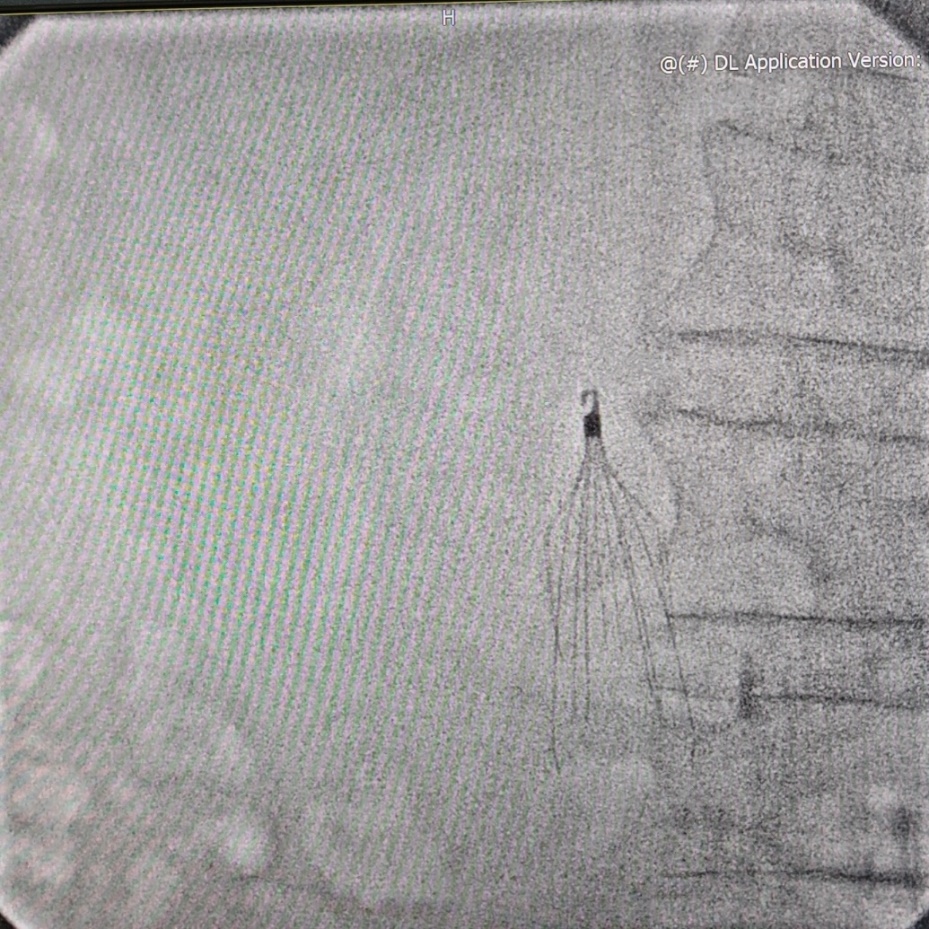

7月6日下午,经超声引导下颈内静脉穿刺成功后,手术正式开始。由于颈内静脉更直,送入递送系统过程中有系统头端压力过大的风险。为避免此风险,需在术中全程X线透视并保持递送系统处于弯曲状态,采用多角度X线透视以确保起搏器始终处于间隔位置。顺利进入27Fr的传送鞘管后起搏器于间隔部位释放成功,参数满意。

由于经颈内静脉途径做牵拉试验时,固定翼的活动度不易观察,手术团队也在多角度多体位反复确认后得以通过牵拉试验。手术用时仅30分钟,术后第一天患者下地活动,穿刺部位加压包扎4—6小时后改为普通包扎,程控提示起搏器起搏与感知功能良好。